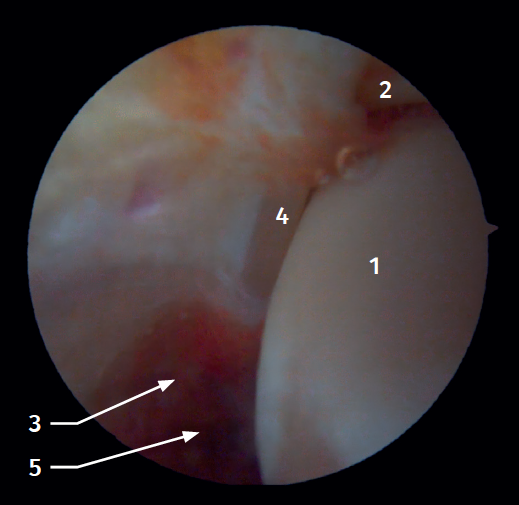

Arthroscopic anatomy of the syndesmosis

Anterior arthroscopic view

Twenty percent of the ATFL is intra-articular(7). On adopting an anteromedial access of the ankle, directing the arthroscope laterally, we can see the distal fibers of the ATFL with their oblique distribution and their continuation with the anterior talofibular ligament (Figure 2). If we move into the tibiotalar joint, we see the distal tibiofibular joint with the syndesmotic recess occupied by synovial tissue (Figure 3).

Posterior arthroscopic view

From the posterolateral approach we identify the lateral (fibular) malleolus and, from here, we visualize the intra-articular fibers of the PTFL, which run obliquely and insert into the distal portion of the tibia. We also see the distal thickening of the PTFL (transverse ligament) in continuity with the posterior lip of the distal tibia (Figure 4).